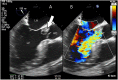

Case summary: This case describes a man with long-lasting complaints of progressive dyspnoea caused by heart failure due to total destruction of the aortic and mitral valve as a result of T. whipplei endocarditis, diagnosed with serum polymerase chain reaction. The patient was treated with ceftriaxone and prolonged co-trimoxazole therapy and surgical replacement of the aortic and mitral valve. He was discharged to a rehabilitation centre.